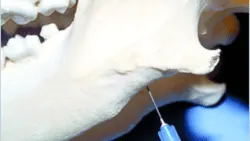

Step-by-Step: Maxillary Nerve Block

The maxillary nerve block affects the bone, teeth, soft tissue, and palatal tissue on the infiltrated side.

1. With the patient's mouth open, palpate the notch where the zygomatic arch meets the bone surrounding the last maxillary molar.

2. Insert the needle directly adjacent to the bone at this level.

3. Hold the needle perpendicular to the hard palate.

4. Advance the needle dorsally to a level just beyond the extent of the root tips of the last molar.

5. Aspirate and slowly inject.

A needle is positioned near the joint of a canine skull, demonstrating a technique for intra-articular injection. The image highlights the anatomical landmarks relevant for veterinary procedures involving joint therapy.